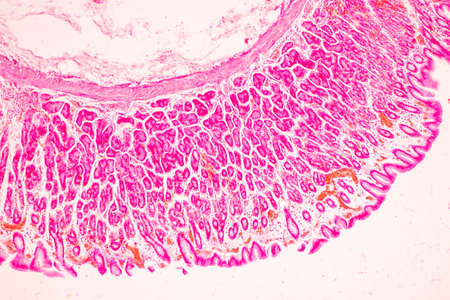

Cross section of human skin under microscope view for education in laboratory.